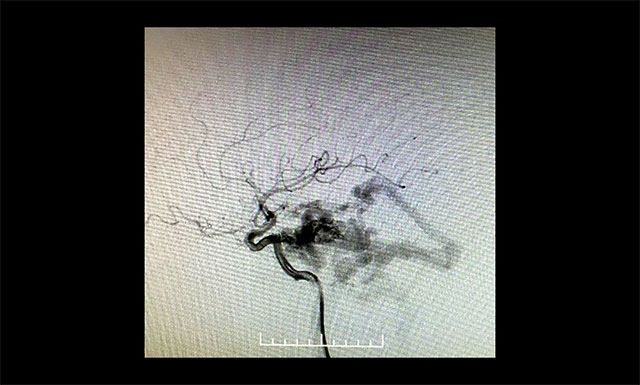

DSA 检查显示,左侧天幕区硬脑膜动静脉瘘,瘘口血流大,供血来源广泛,引流静脉有瘤样扩张。

▲ DSA检查显示,左侧天幕区硬脑膜动静脉瘘